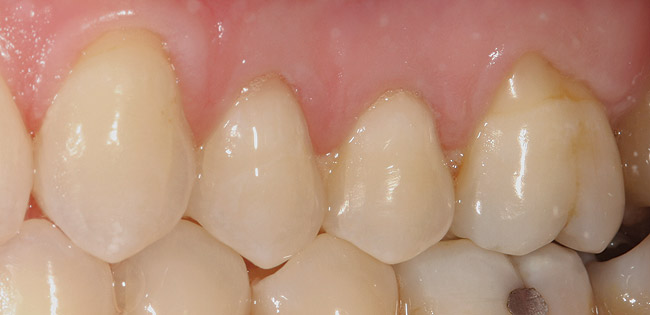

No Change in Root-Surface Quality (NC)

A patient with no change in root-surface quality (Figure 1) will present with gingival recession that exposes the root surfaces and no change due to disease is noted. Clinically, the root surfaces are firm, smooth, and velvety upon exploration. No color changes are noted.

Figure 1  This patient presented with generalized gingival recession of the mandibular anterior teeth. There were no changes in the root surfaces that would indicate the beginning of the demineralization process. Although no surface demineralization process had occurred, these root surfaces would respond to remineralization therapy. The positive changes may include: hard, shiny root surfaces and a reduction in dentinal hypersensitivity.

Figure 1